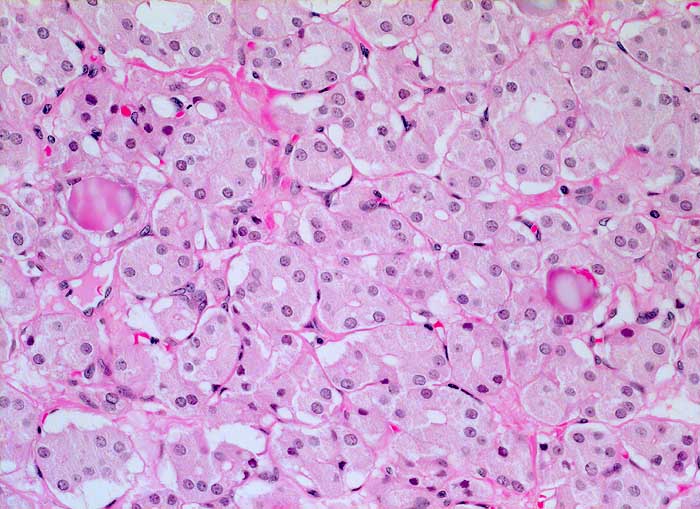

PathoPic ID 6037 - Mikrofollikuläres Schilddrüsenadenom (toxisches Adenom)

Mikrofollikuläres Schilddrüsenadenom (toxisches Adenom)

Das Adenom besteht aus monomorphen kleinen Follikeln mit hochprismatischem aktiviertem Epithel. Die Follikel enthalten wenig oder gar kein Kolloid.

Makroskopisch solitärer bunter Knoten von 6cm Durchmesser.

Toxischer Knoten Schilddrüse rechts.

Zytologisch wurde aufgrund der zahlreichen vorhandenen Epithelien und einzelner Mikrofollikel eine follikuläre Neoplasie diagnostiziert.